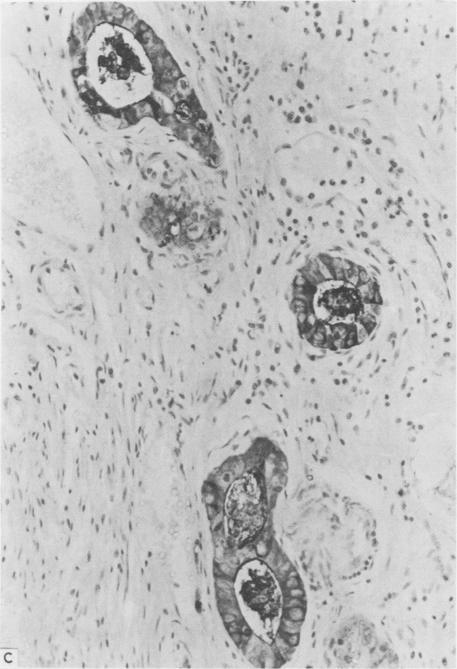

An immunoperoxidase technique was applied to formalin and Helly fixed paraffin wax sections from cases of ulcerative colitis complicated by dysplasia and carcinoma for carcinoembryonic antigen and components of the colonic secretory immunoglobulin system--namely, secretory component, IgA, and J chain. Sections from both resection specimens and mucosal biopsies were available. Intensity of immunostaining was assessed qualitatively. There was appreciable variation in expression of carcinoembryonic antigen and secretory component antigens. Carcinoembryonic antigen stained heavily in dysplasia and carcinoma while these tissues showed only focal light staining for secretory component. Normal tissue stained heavily for secretory component. The variation in staining intensity for both carcinoembryonic antigen and secretory component in inflamed and regenerative mucosa precluded their use as a reliable diagnostic aid in discriminating these tissues from true dysplasia. Loss of secretory component production or transport or both may be incurred during malignant change, but it should not be assessed as an isolated index of epithelial maturity. The relation with mucosal plasma cells warrants further study to determine more fully the factors affecting tissue secretory component expression.

免疫过氧化物酶技术应用于福尔马林和Helly固定的石蜡切片,这些切片取自溃疡性结肠炎并发发育异常和癌的病例,用于检测癌胚抗原和结肠分泌型免疫球蛋白系统的成分,即分泌成分、IgA和J链。切除标本和黏膜活检的切片均可用。免疫染色强度进行定性评估。癌胚抗原和分泌成分抗原的表达存在明显差异。癌胚抗原在发育异常和癌组织中染色较深,而这些组织中分泌成分仅呈局灶性淡染。正常组织分泌成分染色较深。炎症和再生黏膜中癌胚抗原和分泌成分染色强度的变化,使其无法作为区分这些组织与真正发育异常的可靠诊断辅助指标。恶性改变过程中可能会出现分泌成分产生或运输或两者的丧失,但不应将其作为上皮成熟度的单一指标来评估。与黏膜浆细胞的关系值得进一步研究,以更全面地确定影响组织分泌成分表达的因素。